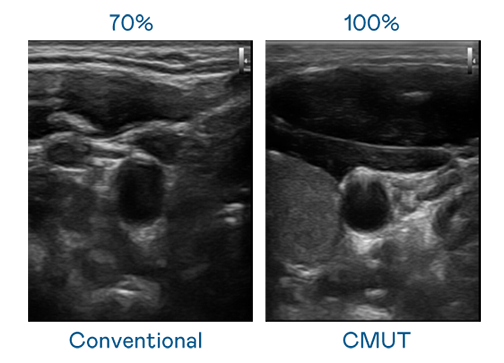

CMUT 技术是一种用电容式微机电元件来产生超音波讯号的技术。与传统 PZT 压电式技术相比,CMUT 频宽增加 30%,更宽频的超音波讯号让影像解析度大幅提升,是实现高影像品质医疗超音波扫描、促进精准医疗发展的关键技术。

大频宽带来超清晰影像

超音波影像的解析度高低,首先取决于探头能发出的讯号频宽。PG CMUT 可提供高清晰的超音波讯号,提供高频宽、高灵敏度、影像纹理细节更高的超音波影像,协助医护人员缩短影像判读时间及利用精准的医疗影像进行诊断。